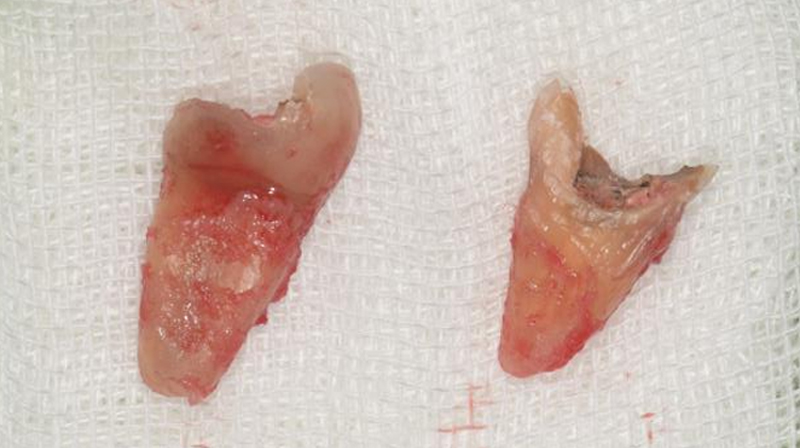

拔除右下第一大臼齒

拔除智齒,固定至第一大臼齒缺牙區域